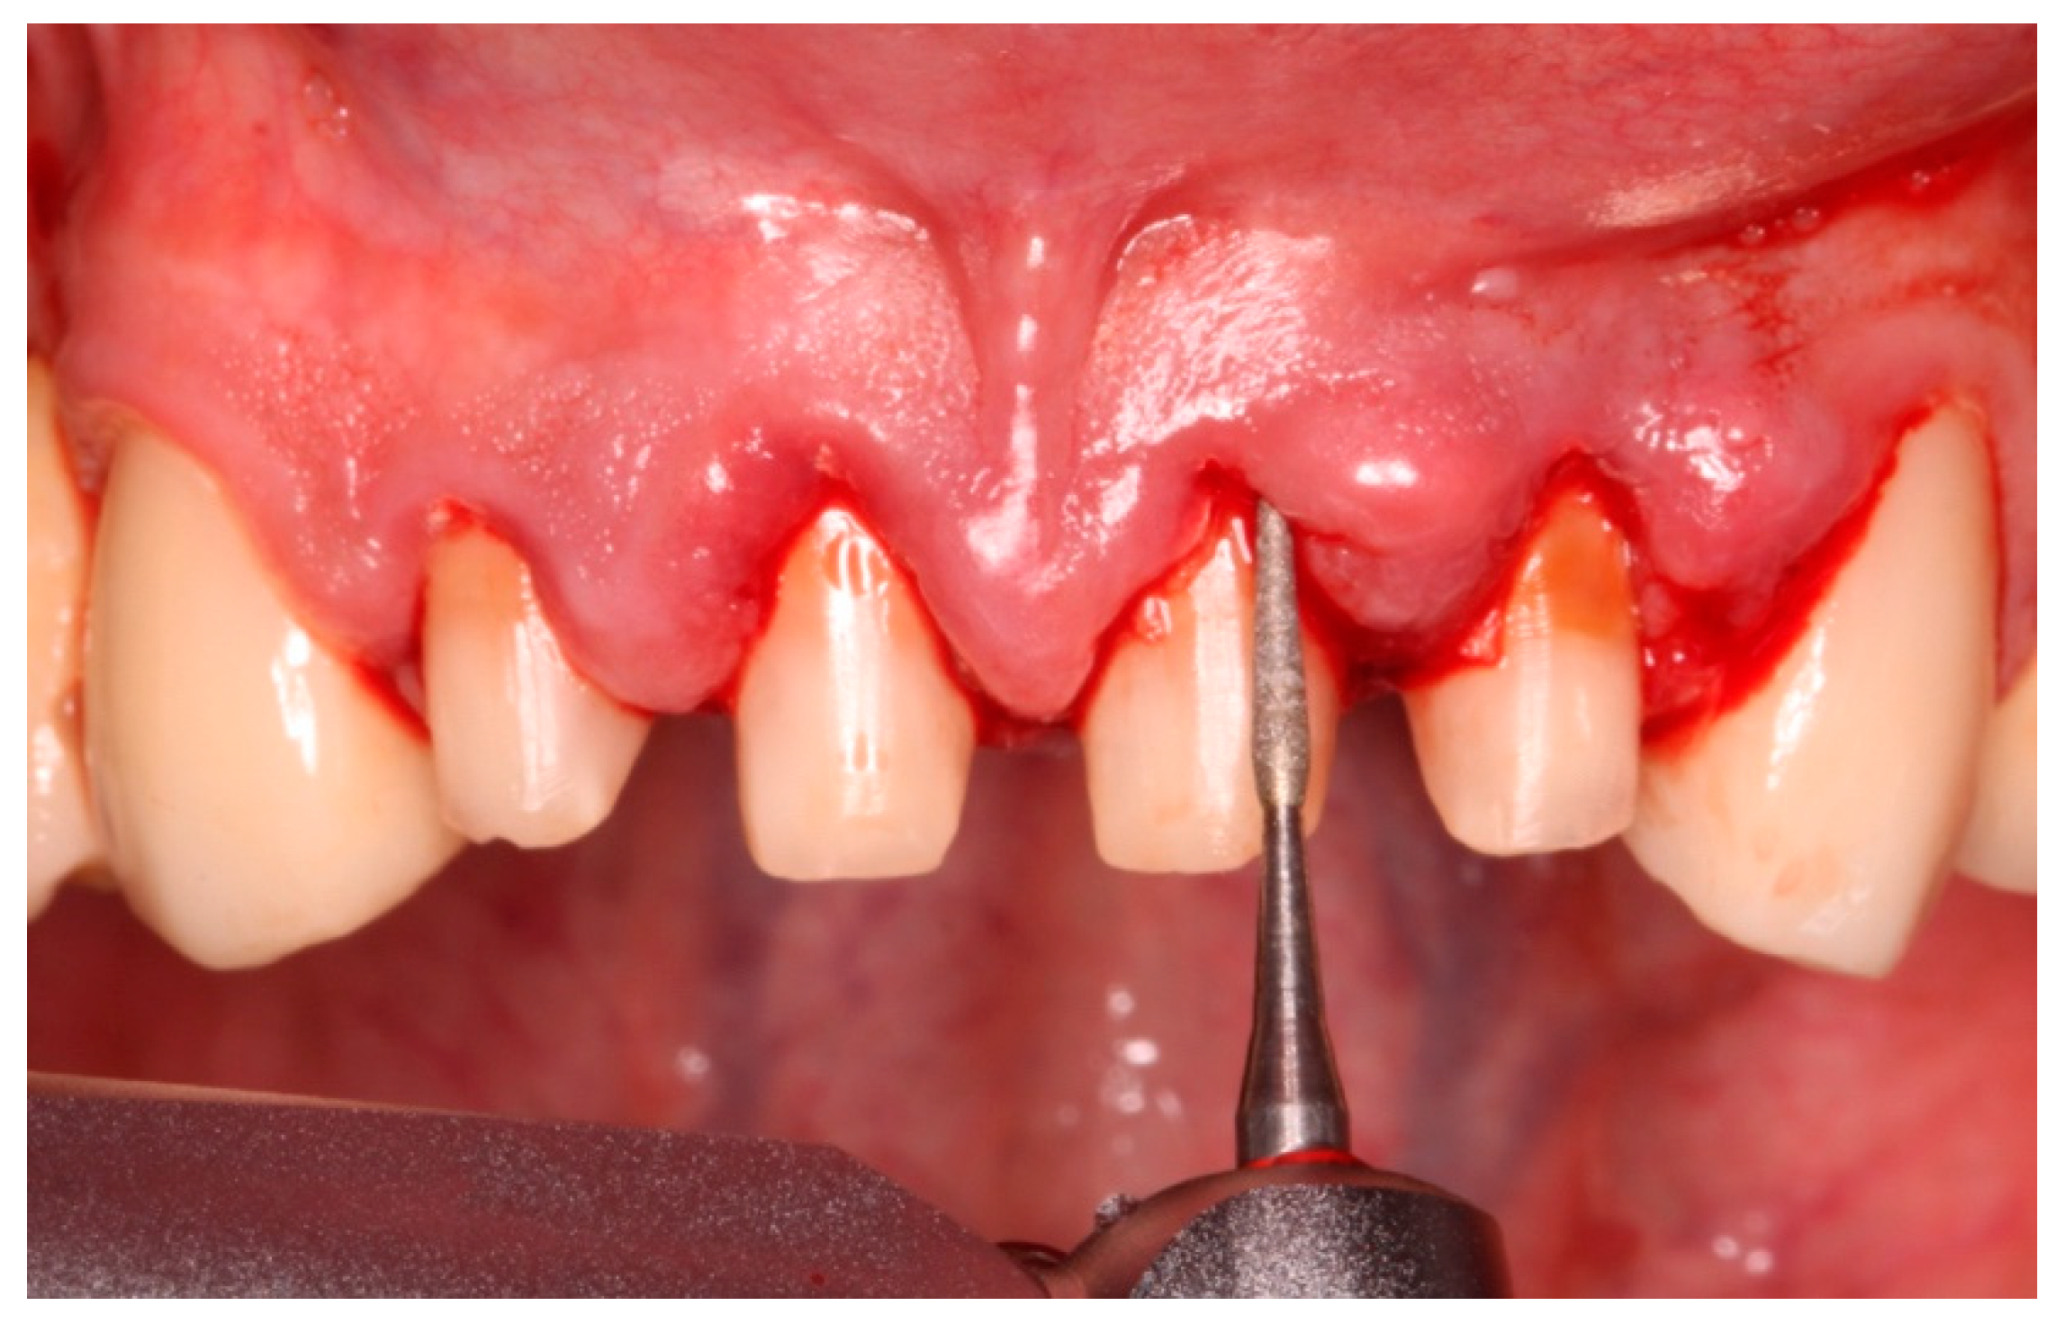

b Preoperative view of gingival recession located at teeth 1611 on Manipulation Of Gingival Tissue For patients with these underlying cardiac conditions, prophylaxis is recommended for all dental procedures that involve. For patients with high cardiac risk, antibiotic prophylaxis is recommended for all dental procedures that involve manipulation of. Prophylaxis is recommended for the patients identified in the previous section for all dental procedures that involve manipulation of. Invasive dental or oral procedures — the. Manipulation Of Gingival Tissue.